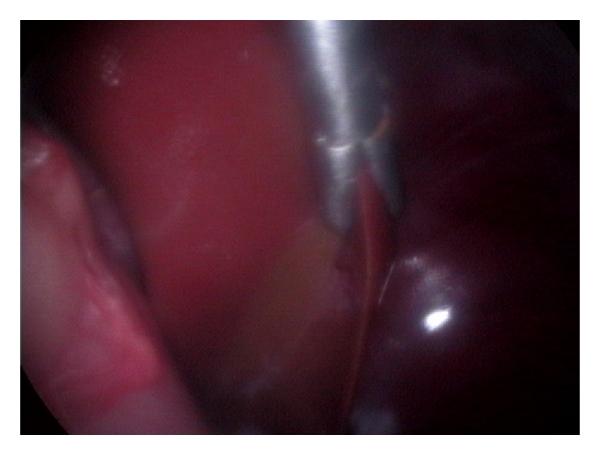

Hepatic disease is often treatable and has a predictable prognosis when a definitive diagnosis is made. The aim of clinicopathological evaluation of hepatobiliary affections is to identify and characterize hepatic damage and dysfunction, identify possible primary causes of secondary liver disease, differentiate causes of icterus, evaluate potential anaesthetic risks, assess prognosis and response to xenobiotics, and monitor response to therapy. This paper describes the different diagnostic methods and imaging techniques employed in diagnosis of hepatobiliary affections in dogs. Besides reviewing the significant clinical manifestations and imaging structural abnormalities in diagnostic approach to different hepatic affections, it also depicts radiographic, ultrasonographic, and wherever applicable, the laparoscopic characterization of different hepatic affections and target lesions encountered in clinical cases presented in the Teaching Veterinary Clinical Complex, COVAS, Palampur in the year 2007-2008.

肝病通常是可治疗的,一旦做出明确诊断,其预后是可预测的。肝胆疾病临床病理评估的目的是识别和描述肝损伤及功能障碍,确定继发性肝病可能的主要病因,鉴别黄疸的病因,评估潜在的麻醉风险,评估预后及对外源化学物质的反应,并监测治疗反应。本文描述了用于诊断犬肝胆疾病的不同诊断方法和成像技术。除了回顾不同肝病诊断方法中的重要临床表现和成像结构异常外,还描述了2007 - 2008年在帕兰普尔兽医临床综合教学中心(COVAS)出现的临床病例中不同肝病及目标病变的放射学、超声学特征,以及在适用情况下的腹腔镜特征。